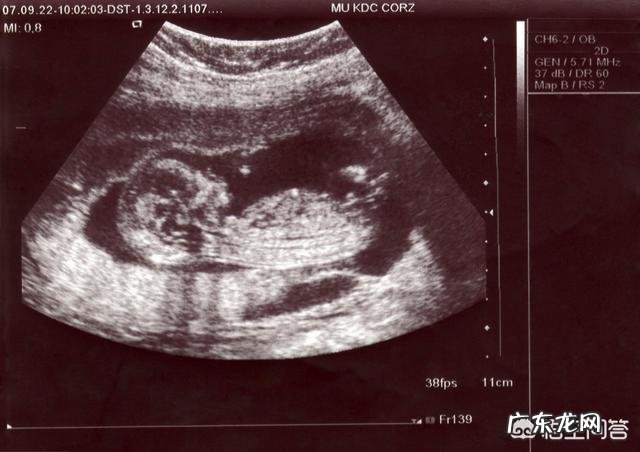

超声检查:确定是否宫内孕、着床情况、双胎绒毛膜性质等 。

超声检查:检查胎儿发育情况,是否有畸形,同时检查羊水和胎位的情况 。